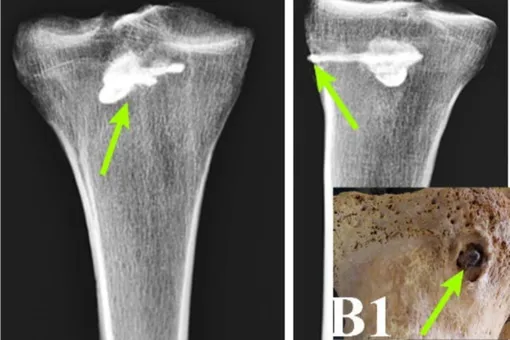

С помощью рентгенофлуоресцентного анализа — метода, определяющего химический состав вещества, — и компьютерной томографии ученые изучили сохранившиеся кости мужчины, а именно большеберцовую кость.

В ней они обнаружили металлический кусок стрелы. Это был не просто обломок, а целый наконечник с тремя лезвиями. Он был 44 мм в длину и 15 мм в ширину. Более того, его реконструкция полностью совпала по стилю с найденными ранее парфянскими стрелами.

Дальнейший анализ позволил ученым увидеть, что при жизни плотная костная ткань начала формироваться вокруг наконечника. Это означает, что после ранения человек остался жив, и его тело начало процесс заживления.